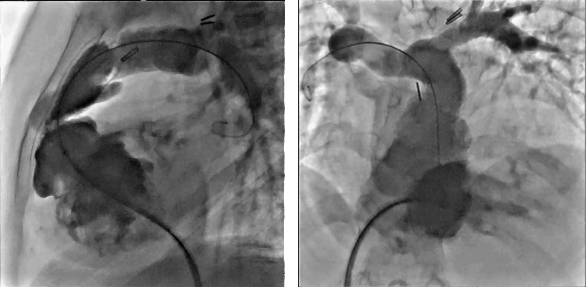

Вроджені вади серця можуть впливати на структуру серця, артерії та вени і часто потребують втручання в ранньому віці (дитяча кардіологія).

Переваги для дитячої кардіології:

Оснащується системою гемодинамічних досліджень QMAPP®

Найбільш компактна, сучасна та вдосконалена система вимірювання гемодинаміки.

Простий у користуванні пристрій, що приєднується до ангіографу всього одним лише одним кабелем. Оснащується програмним забезпеченням, яке дійсно дозволяє зосередити увагу на своїх пацієнтах.

Програмне забезпечення:

Блок сигналів:

QMAPP забезпечує вимірювання:

CAAS vFFR (судинний фракційний резервний кровотік, так званий віртуальний) обчислює падіння тиску в коронарних судинах без необхідності використання провідника з датчиком тиску. Модуль vFFR будує 3D-реконструкцію на основі двох ангіографій і оцінює падіння тиску, в результаті чого отримує значення vFFR. Крім того, 3D-реконструкція дозволить оцінити ступінь тяжкості та відсоток стенозу.

Інформація про функціональне ураження:

Інформація про анатомічне ураження:

Переваги: